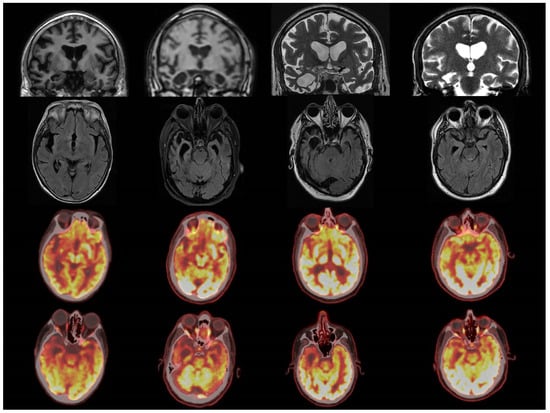

3.3. Concordance with PET

- Radiological considerations